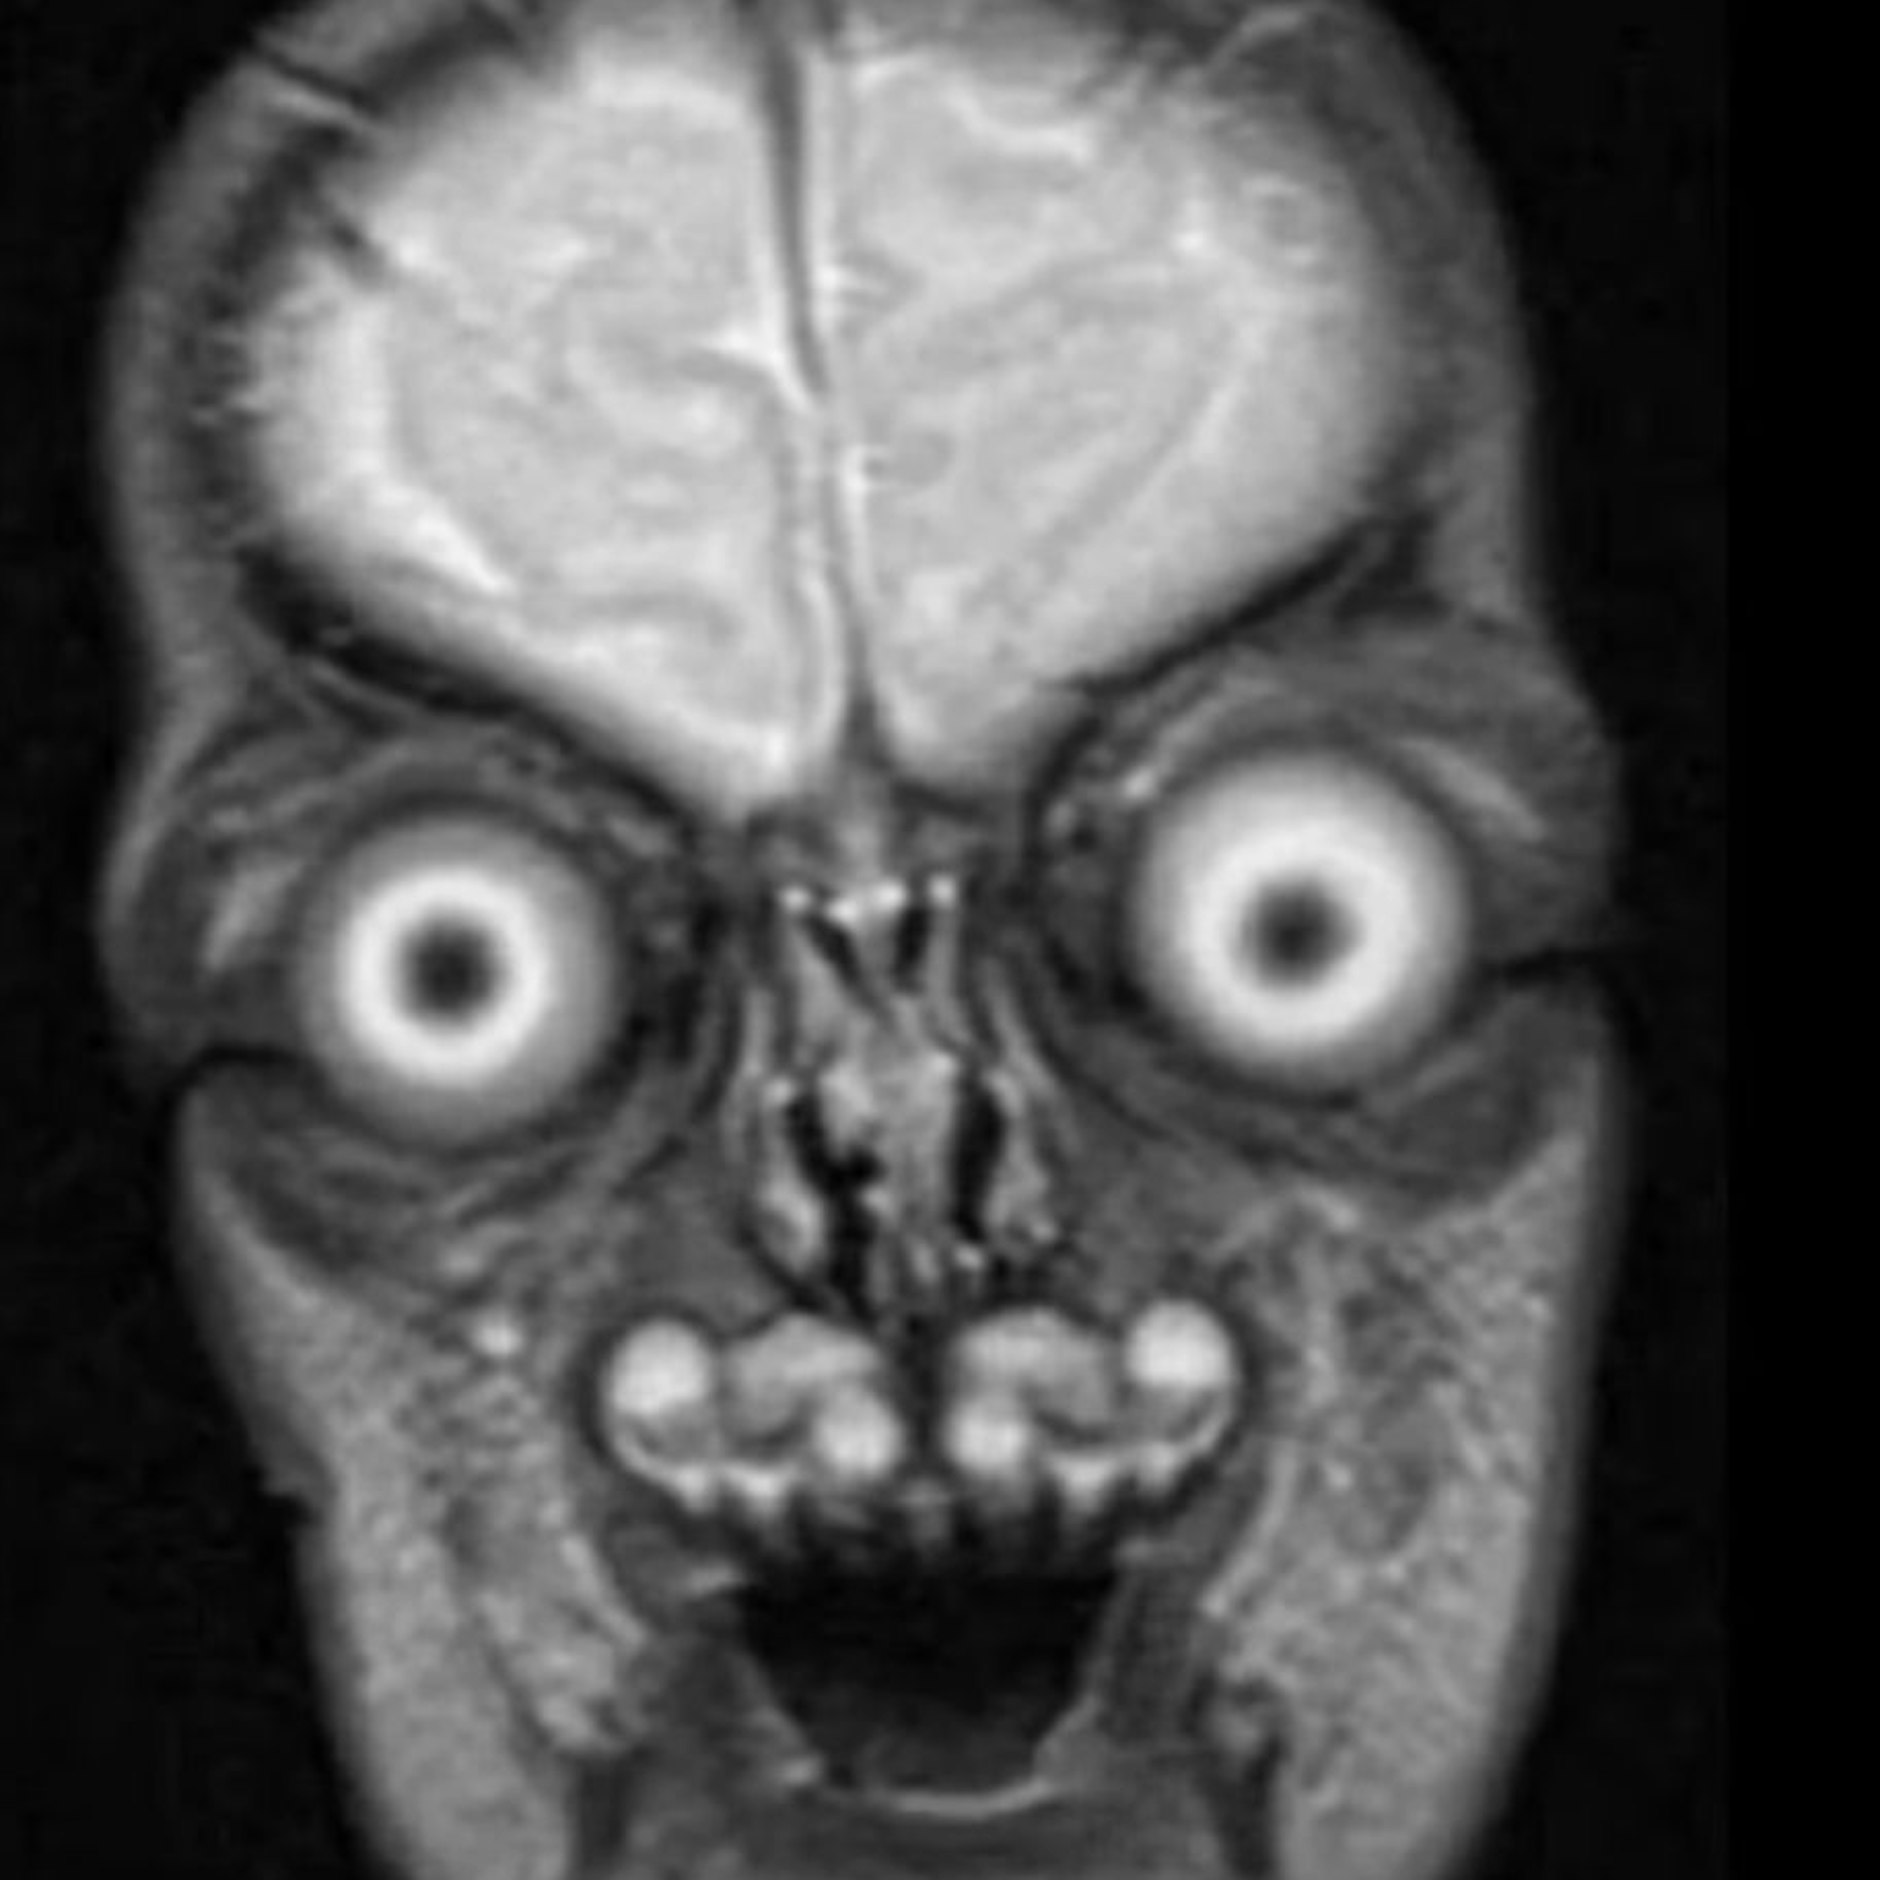

„Sind das Aliens?“ „Ich bekomme Albträume!“ Die MRT-Scans von Föten im Mutterbauch sorgen für Entsetzen auf Social Media. Denn die Babys haben übergroße Augen und teuflische Grinsen – womit sie durchaus Außerirdische aus einem Hollywood Science Fiction-Film sein könnten.

Eine Twitter-Userin namens Katie hatte ein Dutzend schwarz-weiß Fotos von Föten-MRT-Scans gepostet. Sie stammen von einem Projekt der Harvard Medical School. Sie schrieb dazu: „Das ist der wahre Grund, warum Frauenärzte sich gegen MRTs während der Schwangerschaft aussprechen. Die Babys sehen aus wie Dämonen und würden den Müttern Albträume geben!“

Viele Kommentatoren waren deshalb auch geschockt von dem, was sie sahen: „Die sehen aus wie aus einem Horror-Film von Tim Burton!“

Die Webseite „Snopes“ versuchte sogar zu belegen, dass es sich um Fälschungen handeln muss – und wurde enttäuscht. Ein Forscher der Universität von Wisconsin bestätigte aus eigener Erfahrung, dass die Babys im Bauch wirklich so in MRTs aussehen – und schickte sogar eigene Fotos.